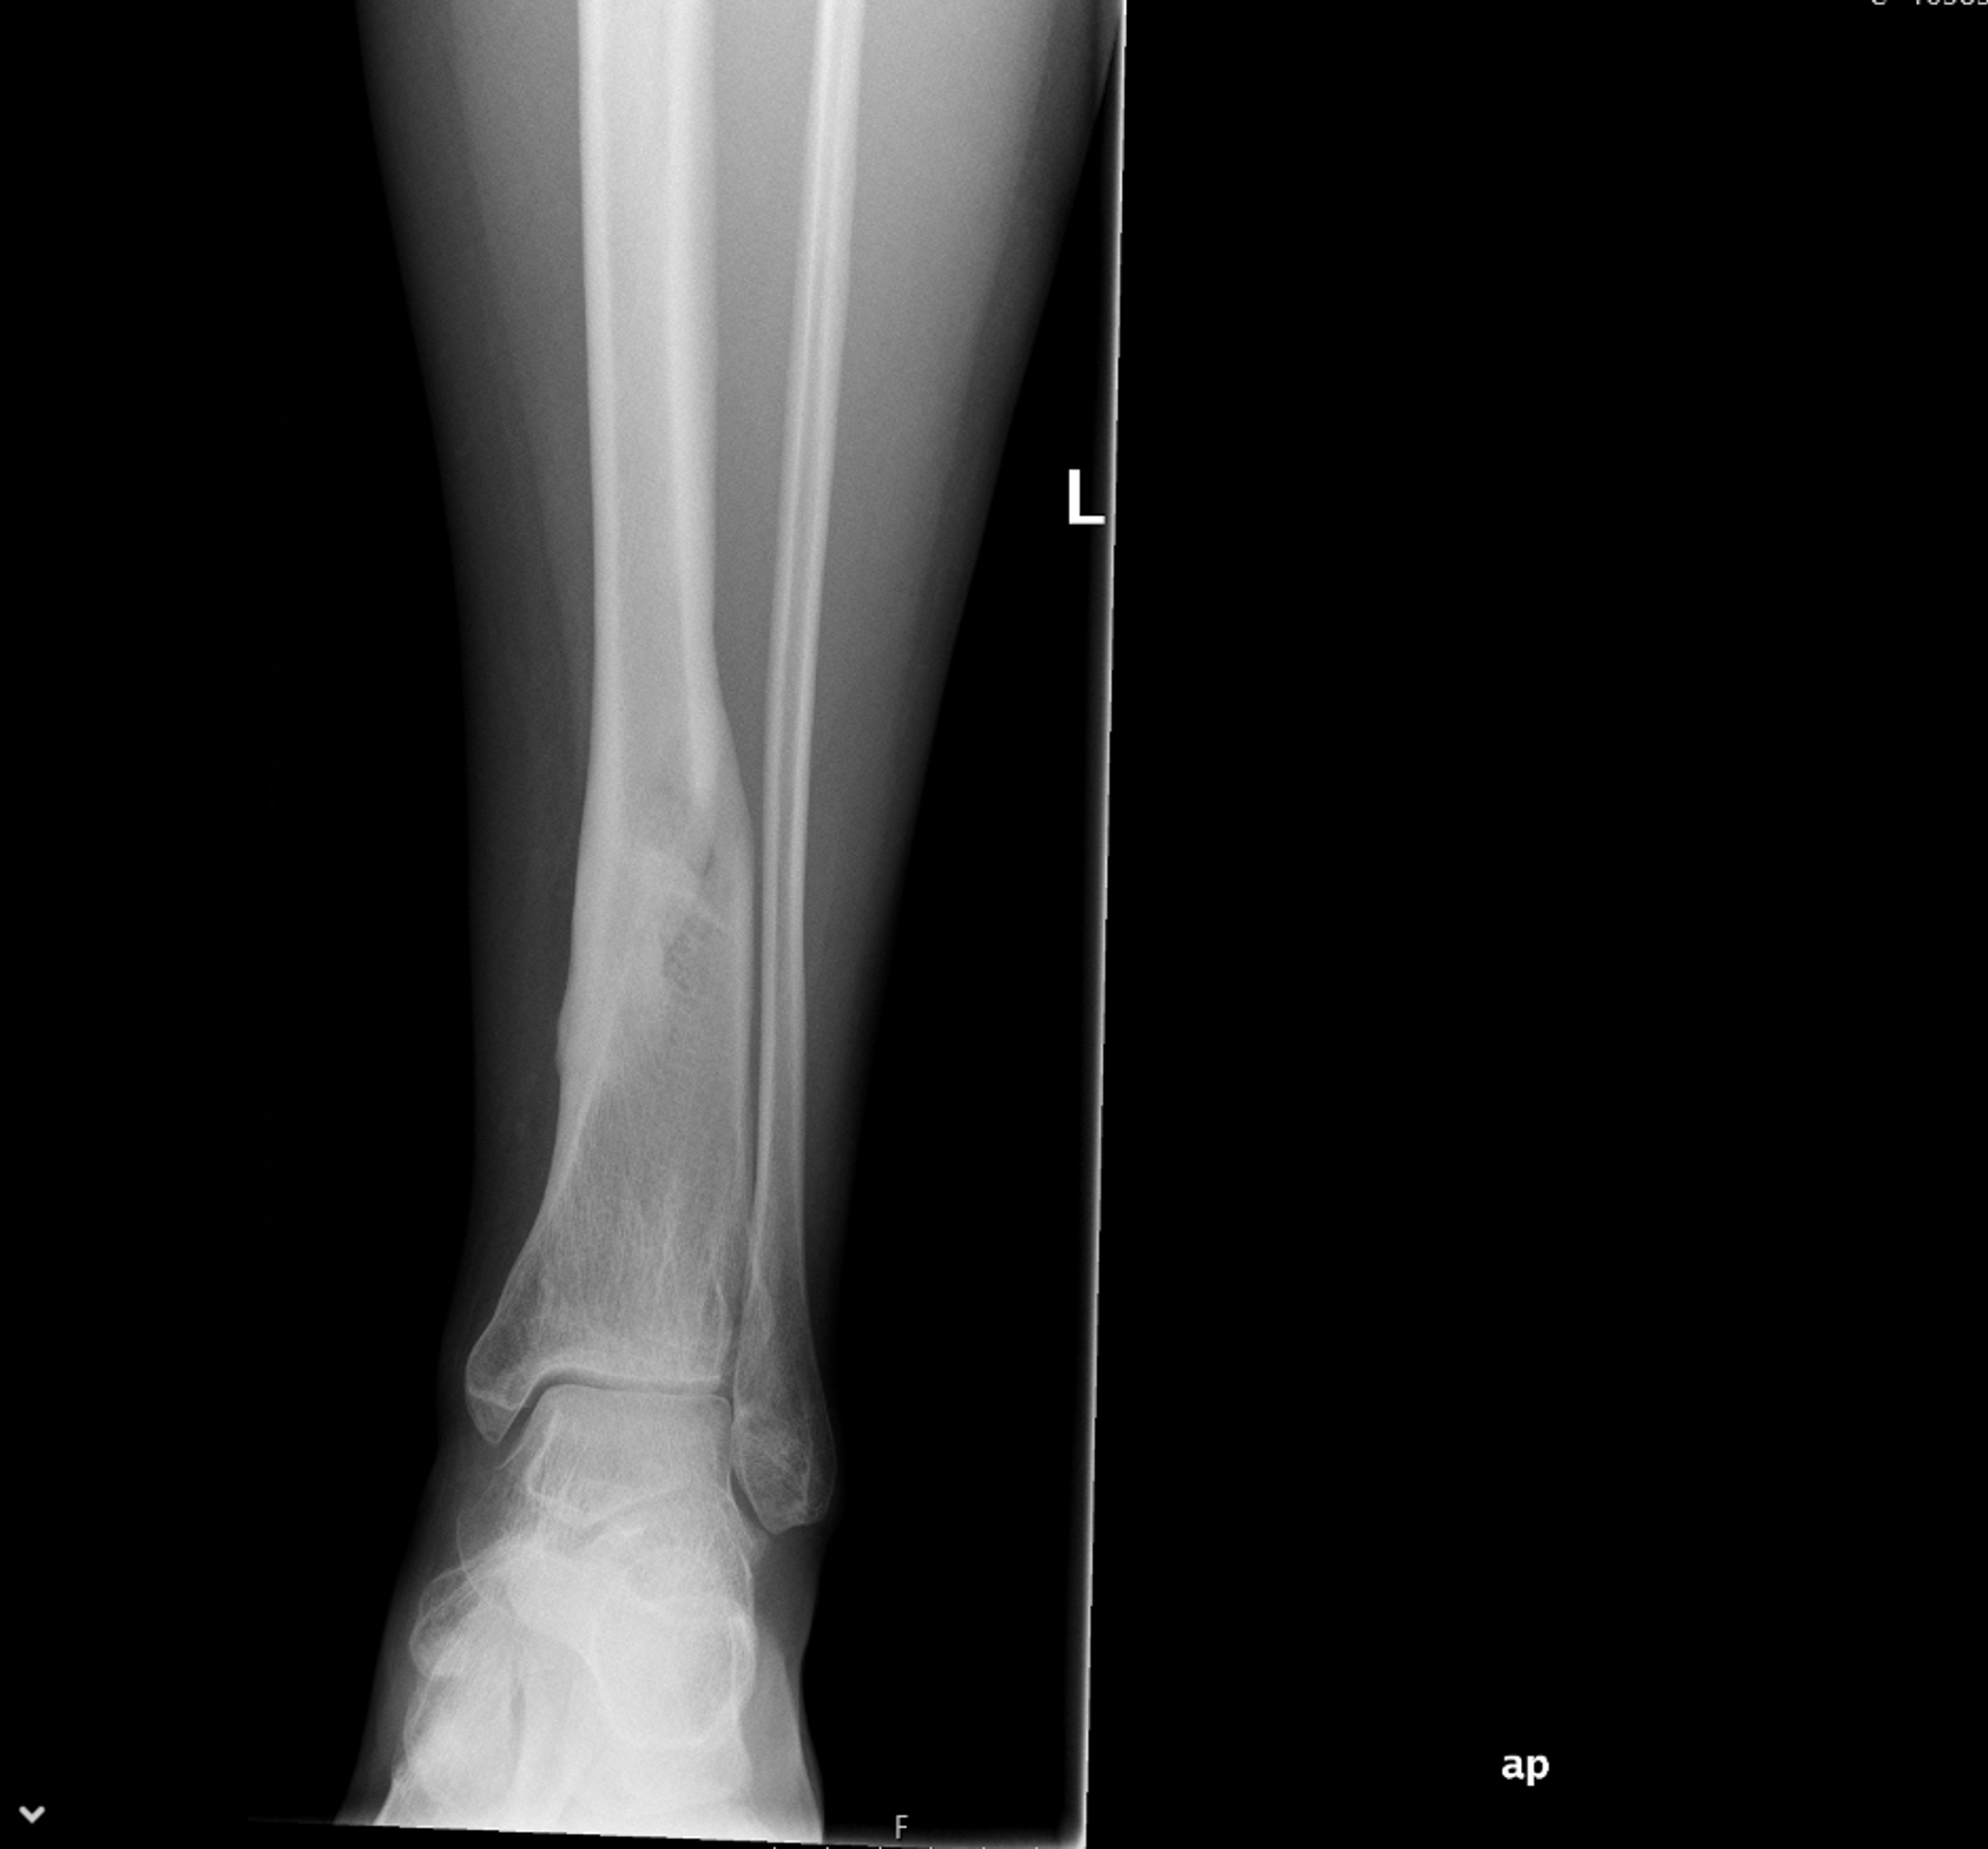

Xrays and Slides nonunion of fracture distal tivbia Non Union Fracture X Ray Comminution, bone loss, or segmental patterns) have a higher degree of soft. — this is the most common 'natural' healing process, whereby the fracture ends are placed close to each other (but not apposed), with. fracture patterns in higher energy injuries (i.e.: nonunions occur when the bone lacks adequate stability, blood flow/nutrition, or both. They also are. Non Union Fracture X Ray.